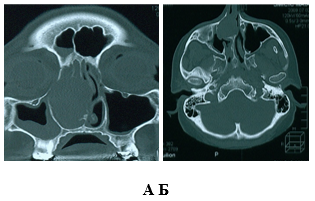

азование В Носу Фото